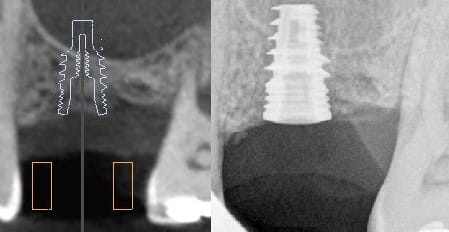

pour vous donner une petite idée chaque guide revient entre 25 et 40 euros ! Pas d'abonnement, pas de licence !

Bonjour pour vous répondre la précision de la form2 est de 25 microns, celle de la robox 100 microns. Nous faisons tout types de guides ( full guided, pilote, muqueux, dentaire, osseux, mixte...). L'avantage de ce procédé c'est que nous maîtrisons tout les paramètres ( dont l'enfoncement des forets puisque c’était votre deuxième question)

Blueskyplan est un logiciel gratuit de planification...grâce a ce logiciel tu vas aussi pouvoir réaliser un guide chirurgical numerique en format STL. Ce qui devient payant c'est alors d'exporter ce guide en format STL (entre 11 et 20 euros par cas en fonction du nombres de cas que tu achètes) . Du coup en faisant notre formation tu auras tes 6 premières exportations gratuites et tu n'auras plus qu'a imprimer les guides chez toi avec le prix de la resine ( de qqs centimes a qqs euros en fonction de l'imprimante )